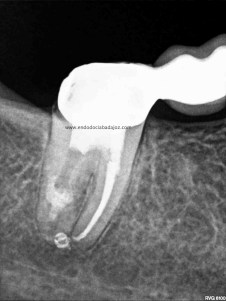

Hemos llamado a revisión a la paciente en varias ocasiones ( 6 meses y 9 meses)

(revision a los 6 meses) (revisión a los 9 meses)

Como podemos observar, la lesión periapical ha regenarado: